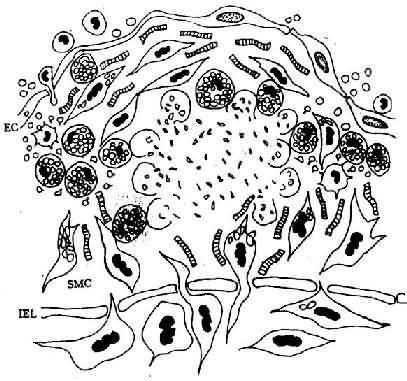

内皮下间隙(SES)大量巨噬细胞源性泡沫细胞聚集,中膜SMC穿过内弹性膜(IEL)窗孔迁入内膜,增生并摄取脂质,内膜隆起及变形EC:内皮细胞病变的进展:已知OX-LDL具有细胞毒性,当大量OX-LDL被巨噬细胞摄取,超过了其清除能力时可引起泡沫细胞的坏死,导致细胞外脂质核心形成。加之,SMC大量增生,穿插于巨噬细胞源性泡沫细胞之间,产生胶原、弹性纤维及蛋白多糖,使病变演变为纤维斑块(图8-3)。

图8-3 脂纹的进展

泡沫细胞坏死及细胞外脂质核心形成,SMC继续增生,产生胶原、弹性纤维及蛋白多糖,使病变演变为纤维斑块